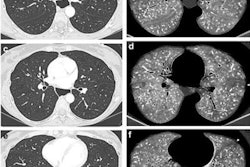

Distal radius fractures make up 17% of all bone breaks in patients who present in the emergency department with these injuries. Typically, treatment is staged using x-ray to determine whether a patient will need bone substitutes during surgery, but DECT could help assess volumetric bone mineral density even more effectively, the investigators noted.

"The purpose of this study was to evaluate the feasibility of dual-energy CT-based BMD assessment from routine examinations of the distal radius and the relationship between the obtained BMD values and the occurrence of distal radius fractures, bone nonunion, and surgical bone substitute use," they wrote.

To this end, the team conducted a study that included 263 patients who underwent DECT on the distal radius between January 2016 and December 2022. Of these, 192 were diagnosed with fractures. The researchers used CT images and health records to determine fracture severity and to assess how surgery was managed and incidence of bone nonunion.